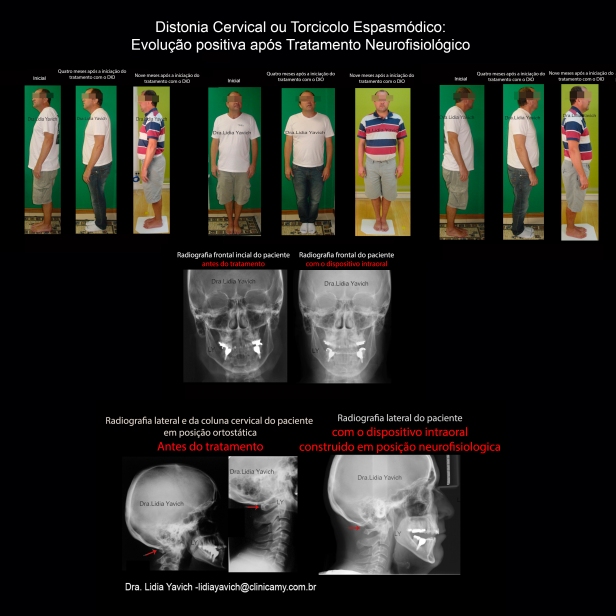

Comparação da imagem frontal do paciente: inicial e quatro meses após o uso do DIO. Notasse uma importante melhora no posicionamento da cabeça e ombros

Comparação da imagem do perfil direito do paciente: inicial e quatro meses após o uso do DIO. Notasse uma importante melhora no posicionamento da cabeça e ombros

Comparação da imagem do perfil esquerdo do paciente: inicial e quatro meses após o uso do DIO. Notasse uma importante melhora no posicionamento da cabeça e ombros

Radiografia Lateral do paciente com o dispositivo em posição neurofisiológica. NOTASSE o espaço entre o arco do ATLAS e o Occipital que não existia na radiografia lateral inicial.

Radiografia Lateral do paciente com o dispositivo em posição neurofisiológica. NOTASSE o espaço entre o arco do ATLAS e o Occipital que não existia na radiografia lateral inicial. Radiografias frontais do paciente comparativas antes do tratamento e com o dispositivo intraoral, o paciente consegue manter a cabeça reta.

Radiografias frontais do paciente comparativas antes do tratamento e com o dispositivo intraoral, o paciente consegue manter a cabeça reta.

Comparação das radiografias laterais e da coluna cervical antes do tratamento e com o dispositivo intraoral .NOTASSE o espaço entre o arco do ATLAS e o Occipital que não existia na radiografia lateral inicial.

Comparação das radiografias laterais e da coluna cervical antes do tratamento e com o dispositivo intraoral .NOTASSE o espaço entre o arco do ATLAS e o Occipital que não existia na radiografia lateral inicial.

Comparação da imagem frontal do paciente: inicial, quatro e nove meses após o uso do DIO. O paciente teve uma recuperação na postura fisiológica.

Comparação da imagem do perfil direito do paciente: inicial quatro e nove meses após o uso do DIO. O paciente teve uma recuperação na postura fisiológica.

Comparação da imagem do perfil esquerdo do paciente: inicial,quatro e nove meses meses após o uso do DIO. O paciente teve uma recuperação na postura fisiológica.